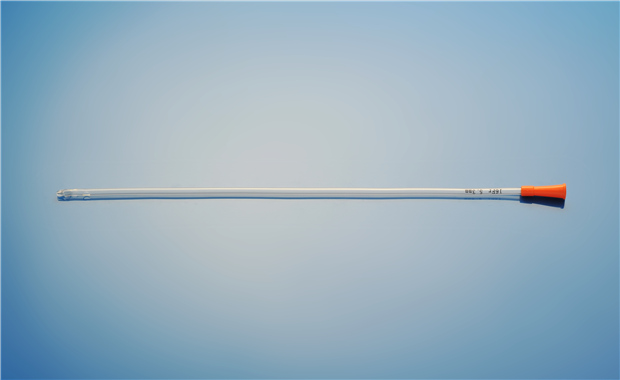

【產品名稱】一次性使用單腔導尿管(PVC兒童型) 【型號規格】6Fr、8Fr��、10Fr 【性能��、主要結構】 由醫用PVC粒料為主要原材料制成��,由排泄錐形接口���、管身、排尿孔組成�����。